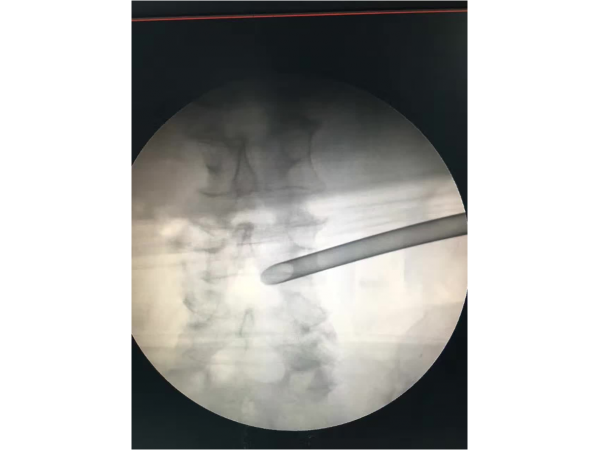

產(chǎn)品說明:椎間孔鏡經(jīng)皮介入輔助下的椎間孔鏡技術(shù),是未來椎間盤突出癥治療的主要微創(chuàng)方法之一。浙江省人民醫(yī)院疼痛科,有國內(nèi)疼痛科最早開

產(chǎn)品說明:1.手術(shù)體位:體位可以采用俯臥位和側(cè)臥位,我們習(xí)慣于采用俯臥位來完成PELD手術(shù)。2.畫線:先畫出腰椎棘突的連線,再畫出雙側(cè)髂嵴

產(chǎn)品說明:腰5/骶1椎間盤突出癥、側(cè)隱窩骨性狹窄。經(jīng)保守治療無效,后主管醫(yī)生陳永紅副主任醫(yī)師為患者實施局部麻醉下微創(chuàng)椎間孔鏡治療,術(shù)

產(chǎn)品說明:這是一位中年男性,有著5年頸段食道腫瘤和2年“胃造瘺術(shù)”病史的多病患者。3月前出現(xiàn)腰部、左臀部及小腿酸痛不適,癥狀逐漸加重